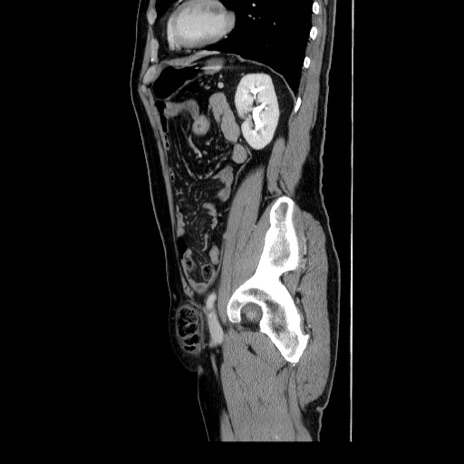

冠状断像